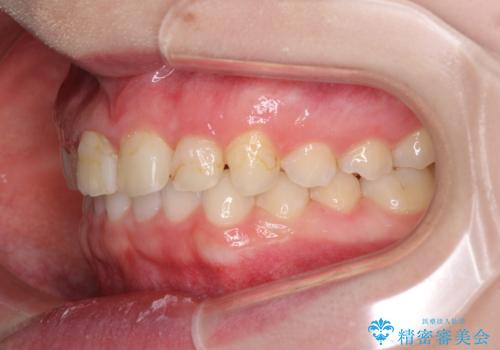

- 前歯の歯並びと虫歯を気にして来院された患者様です。

上下前歯の歯列不正はインビザラインにより歯列を整え、その後に、前歯5本をオールセラミッククラウンにて補綴治療することとしました。

矯正治療前に前歯のむし歯治療を行ったものの、樹脂で充填するには虫歯が広範囲であったため、審美的に問題がありました。

矯正治療にて歯並びを整えた後に、虫歯の大きかった5本の歯をセラミッククラウンにて補綴し、明るい口元になりました。